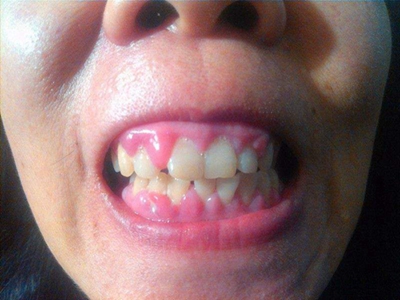

牙龈炎是发生于牙龈组织的炎症,患者可出现牙龈出血伴肿胀、发红、正常形态改变和偶尔不适等症状。本病主要由口腔卫生状况差导致,包括口腔不洁、牙菌斑等,诊断依据临床检查,治疗包括专业牙齿清洁和加强家庭口腔卫生。

牙龈炎可先引起牙齿与牙龈之间的沟(龈沟)加深,然后牙龈充血,炎症围绕一个或多个牙齿,伴牙龈乳头肿胀和易出血。一般无痛,可自行消退,也可维持轻度炎症数年。

牙龈炎常见的病因是口腔卫生差,不良的口腔卫生使牙菌斑沉积于牙齿与牙龈之间,造成龈沟加深,另外牙结石、不良修复体等也可造成牙龈炎的发生。